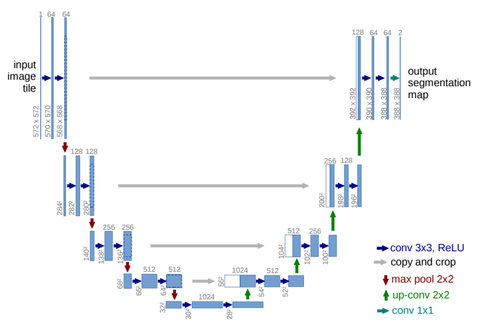

As illustrated in Figure 1, the U-Net network is distinguished by its architecture, which consists of three key components: an encoder, a decoder, and a bottleneck layer. The encoder is responsible for feature extraction and learning from the target object through four stages of convolutional and pooling operations, progressively decreasing the size of the feature maps. During the decoding process, the feature maps are upsampled to restore them to the original image size. Concurrently, the innovative skip connection algorithm integrates shallow and deep feature information. This architecture allows U-Net to effectively learn from small-scale datasets in medical imaging.

| Figure 1. U-Net network architecture diagram |

3. Improved U-Net network

The enhanced U-Net network presented in this paper intelligently integrates the traditional U-Net with elements from Swin-Unet. It utilizes the U-Net structure as the backbone, replacing its convolutional units with Swin Transformer Blocks derived from Swin-Unet. This integration allows for the effective combination of global and local contextual information, thus enhancing segmentation accuracy and robust generalization. Additionally, multi-layer perceptrons are employed at lower levels to model complex features, which significantly reduces both computational complexity and the number of parameters, while still maintaining high segmentation accuracy. The comprehensive framework of this model is showed in Figure 3.

| Figure 3. Schematic of the improved U-Net network structure |